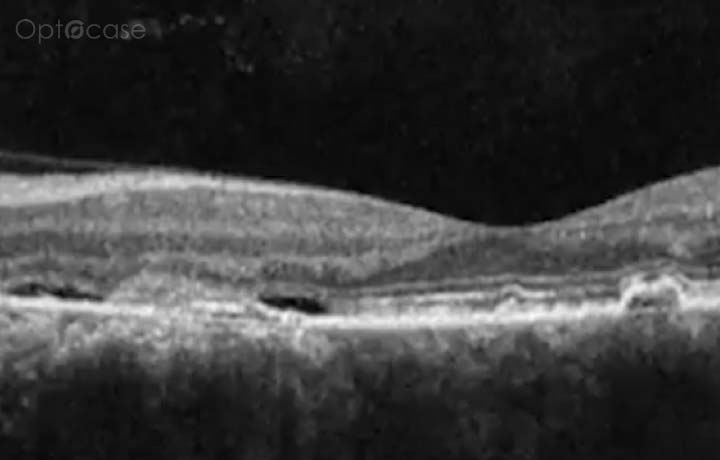

This patient presented with vertical diplopia, normal visual acuity, no afferent pupillary defect, and full extraocular movements. He was unable to fuse Maddox rod lines with prisms except for transient fusion at distance with prisms. His OCT was normal on the right eye, but showed evidence of a past central serous retinopathy (CSR) treated with photodynamic therapy.

The patient was diagnosed with dragged-fovea diplopia syndrome.